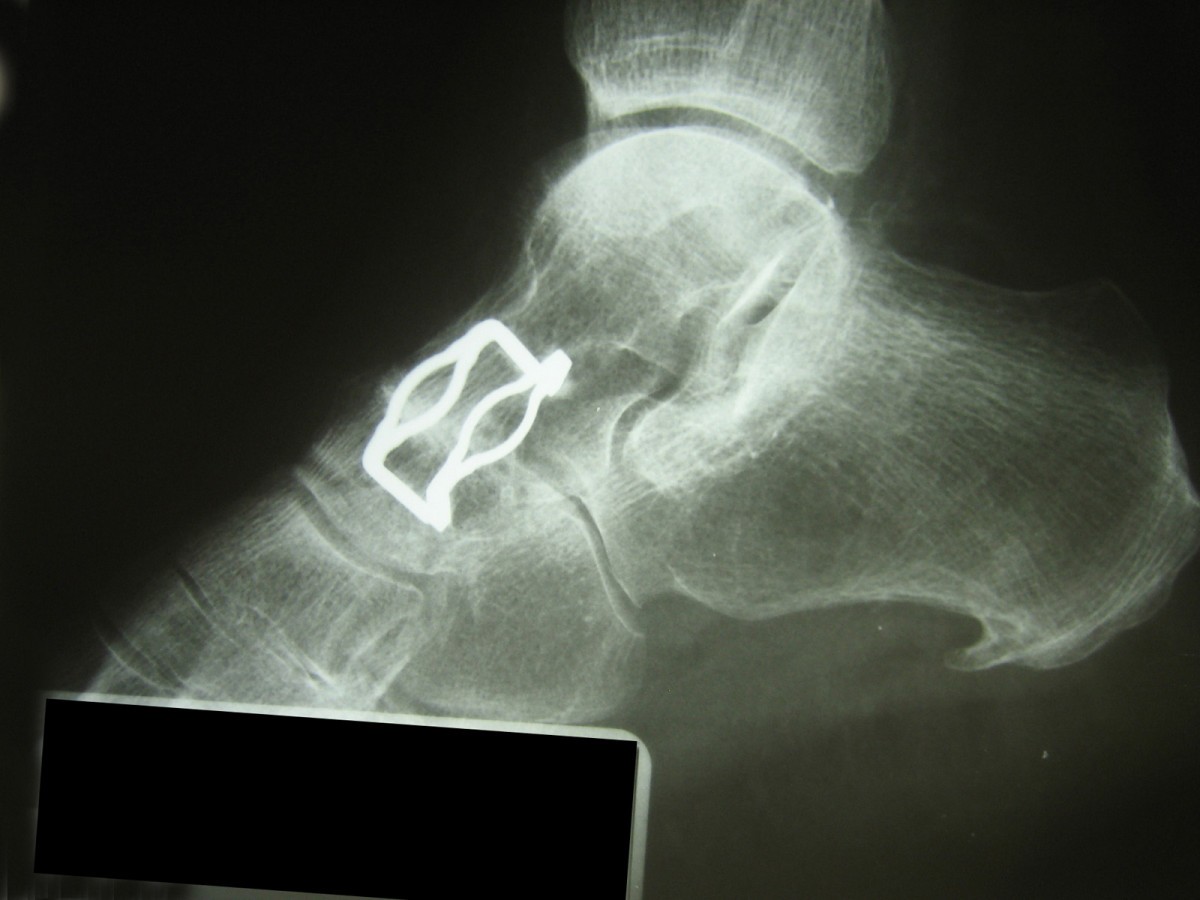

Talonavicular joint fusion surgery. Talonavicular fusions a re done for two main reasons: The surgery may involve the removal of the damaged joint and the permanent stiffening of the bones via plates fixed by screws to facilitate bone fusion as healing occurs. One (2.44%) of these was a female

A talonavicular fusion is a surgical procedure where the talus bone and the navicular bone are fused together. Purpose the talonavicular joint is a central connection of the human foot. On april 28 i am at 4 weeks in a cast.

The technique of fusion involves the removal of cartilage and firm fixing together by. The substantial reduction of movement in the triple joint complex leads to overload of the adjacent joints with development of arthritis in about 30% in the medium term. After the foot is cut open, a portion of the joint and cartilage is amputated and removed.

Fusion of this joint does limit the foot turning down and in and up and out, which may preclude activities on an uneven surface. This is the fusion and realigment of two to four joints around the hindfoot and midfoot. In fact, in many patients, over time, even without running, asd will still happen (2).